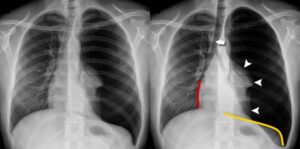

A pneumothorax means a collapsed lung. न्यूमोथोरैक्स का अर्थ है “ढह गया फेफड़ा”। A pneumothorax occurs when air leaks into the space between your lung and chest wall. न्यूमोथोरैक्स तब होता है जब हवा आपके फेफड़े और छाती की दीवार के बीच की जगह में लीक हो जाती है। This air pushes on the outside of your lung and makes it collapse. यह हवा आपके फेफड़े को बाहर से धकेलती है और इसे ढहा देती है। A pneumothorax can be a complete lung collapse or a collapse of only a portion of the lung. एक न्यूमोथोरैक्स फेफड़े का पूर्ण पतन या फेफड़े के केवल एक हिस्से का पतन हो सकता है।